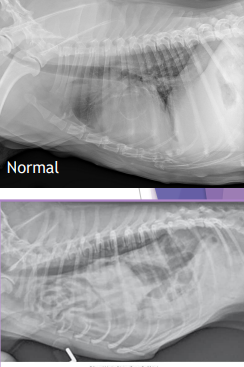

Diaphragmatic Hernia

Et: trauma, pressure gradient disruption, genetic

abdominal organs migrate into thorax, liver is #1

Peritoneopericardial d. hernia (PPDH) → congenital

Sig: Cocker spaniel, Weimaraner, Himalayan, DLH

Cs: shock(acute), dyspnea(chronic), exercise intolerance, ADR

Congenital is asymptomatic

Tears → weakest areas: muscle

Dt: thoracic rads (#1), US, CT

Tx: Sx (8-16w if congenital) (trauma: be ready for anything)

abdominal explore, identify hernia, reduce contents, close defect (absorbable 3-0 PDS, simple continuous, dorsal → ventral), remove air

Caution of adhesions

Do not close the pericardial sac (genetic)

Risk: re-expansion pulmonary edema, abdominal compartment syndrome, ARDS

Do NOT manually re-expand lungs, do not close pericardial sac